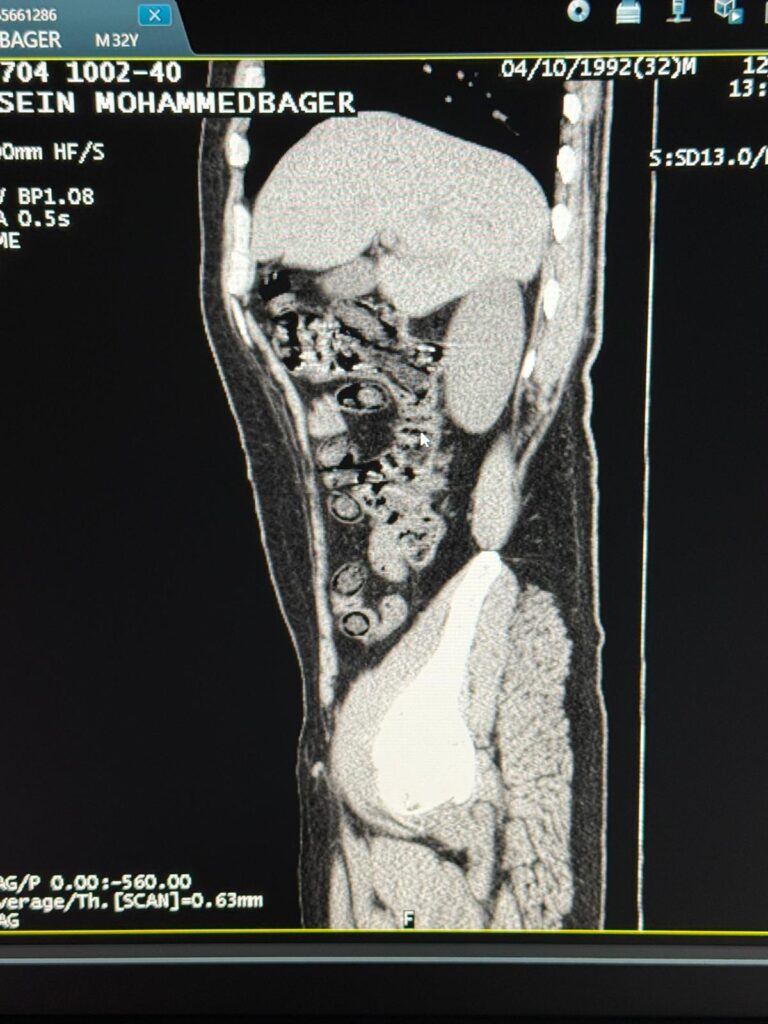

Şahıslar hastaneye sevk edilerek iç beden muayenesine tabi tutuldu. Yapılan tomografi görüntülerinde şahısların midelerinde uyuşturucu kapsülleri olduğu tespit edildi. Şüphelilerin midelerinden çıkarılan toplam 94 kapsül içerisinde, daralı ağırlıkları 928 gram gelen metamfetamin maddesi ele geçirildi.